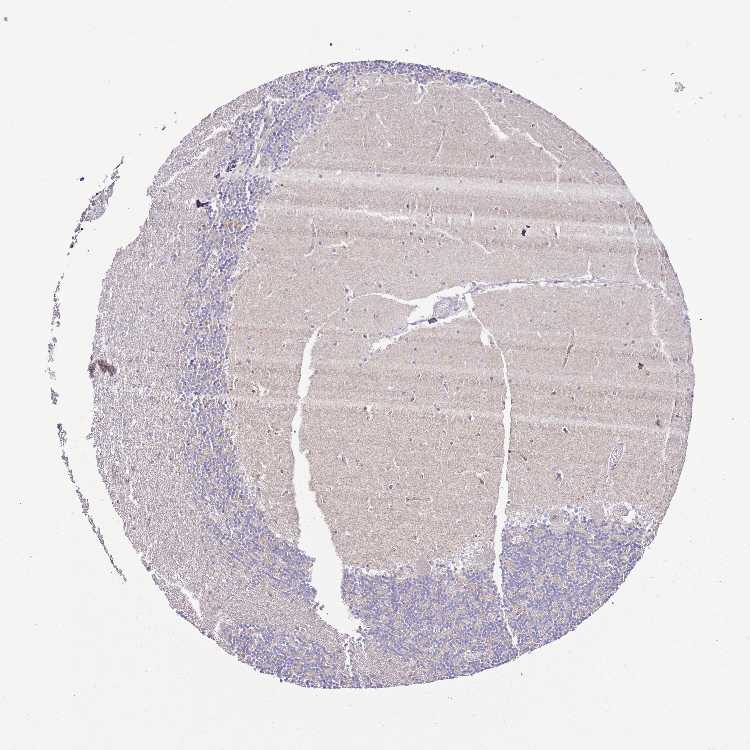

BRAIN CEREBELLUM Show tissue menu

CEREBELLUM - Expression summary

CEREBELLUM - Antibody stainingi

Antibody staining in the annotated cell types in the current human tissue is reported as not detected, low, medium, or high, based on conventional immunohistochemistry profiling in selected tissues. This score is based on the combination of the staining intensity and fraction of stained cells.

Each image is clickable and will lead to virtual microscopy that enables deeper exploration of all samples and also displays staining intensity scores, fraction scores and subcellular localization as well as patient and tissue information for each sample.

Antibody HPA049331Antibody HPA056959

Purkinje cells Not detectedLow

Cells in granular layer Not detectedNot detected

Cells in molecular layer Not detectedNot detected